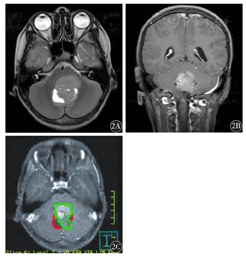

低级别组男性2例,女性7例,平均年龄7.1岁,病程3~180 d,平均45.3 d。MRI检测结果显示,病变发生于小脑5例,四脑室4例;合并梗阻性脑脊液8例;肿瘤总体积(51.1±3.2)mm3;实性成分所占比例为41.7%;合并周围脑实质水肿4例(4/9);肿瘤囊变9例(4/9)。高级别组男性6例,女性7例;平均年龄5.8岁。病程3~60 d,平均23.3 d;MRI检测结果显示,病变发生于小脑蚓部4例,四脑室6例;合并梗阻性脑脊液10例;肿瘤总体积(31.9±1.8)mm3;实性成分所占比例为66.1%;合并周围脑实质水肿4例(4/10);肿瘤囊变4例(4/10)。两组MRI影像结果比较,肿瘤总体积、实性成分所占比例差异有统计学意义(t=2.591,P=0.019;χ2=6.52,P<0.05);其余差异均无统计学意义(均P>0.05)(图1、图2)。

2A:T2WI轴位可见四脑室内实性为主占位性病变,边缘部分可见少许囊变;2B:增强扫描T1WI冠状位肿瘤呈不均匀强化;2C:将原始数据输入Pinnacle三维治疗计划系统,勾画出肿瘤轮廓、肿瘤实性成分区域的范围,得出肿瘤总体积30.3 mm3(红色区域),实性成分体积24.4 mm3(绿色区域);实性成分所占比例为80.5%